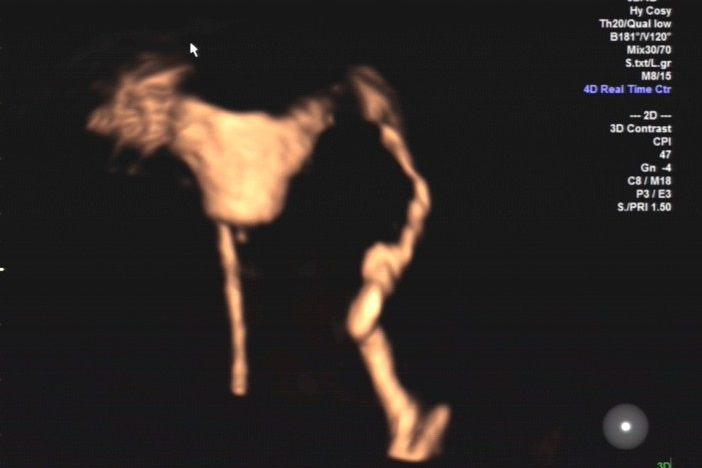

子宫输卵管造影检查,是女性不孕症常规检查项目之一。然而,部分女性却从心理上对它有点儿打怵:传统的子宫输卵管造影检查是在X线下进行的,身体难免会遭受到射线辐射,短时间内不宜怀孕,为弥补这一不足,医院引进子宫输卵管声学造影(HyCoSy)技术,利用超声成像技术使得子宫和输卵管清晰显影。济宁市第一人民医院超声科主任吕镔介绍,该技术具有高清晰的图像分辨,对于输卵管通畅性评价更直观,准确性高,无辐射、无损伤。而且,患者在检查前无需做特殊准备,造影剂在患者体内停留时间短,安全性高,检查完当月即可备孕。

“操作中将造影剂经置入宫腔的导管注入子宫腔和输卵管腔,显示子宫腔和输卵管腔的形态、位置,发现宫腔和输卵管内病变、畸形以及评估输卵管通畅度。超声造影剂对人体无毒害,进入体内后迅速排出,对生殖系统无影响,超声造影技术操作简单、创伤轻微、安全、重复性好及检验输卵管通畅度的高准确性等优势,子宫输卵管超声造影也可使轻度粘连的输卵管得到疏通。”熟练开展该技术的医生陈谦谦介绍,若结果为输卵管通畅,下一月经周期即可实施助孕方案,可能使患者受孕时间提前,故对生殖时间窗影响小。经阴道超声造影探头的出现使患者无需憋尿、不受肥胖及肠道气体的干扰,从而显著提高了诊断的准确率。

双输卵管通畅